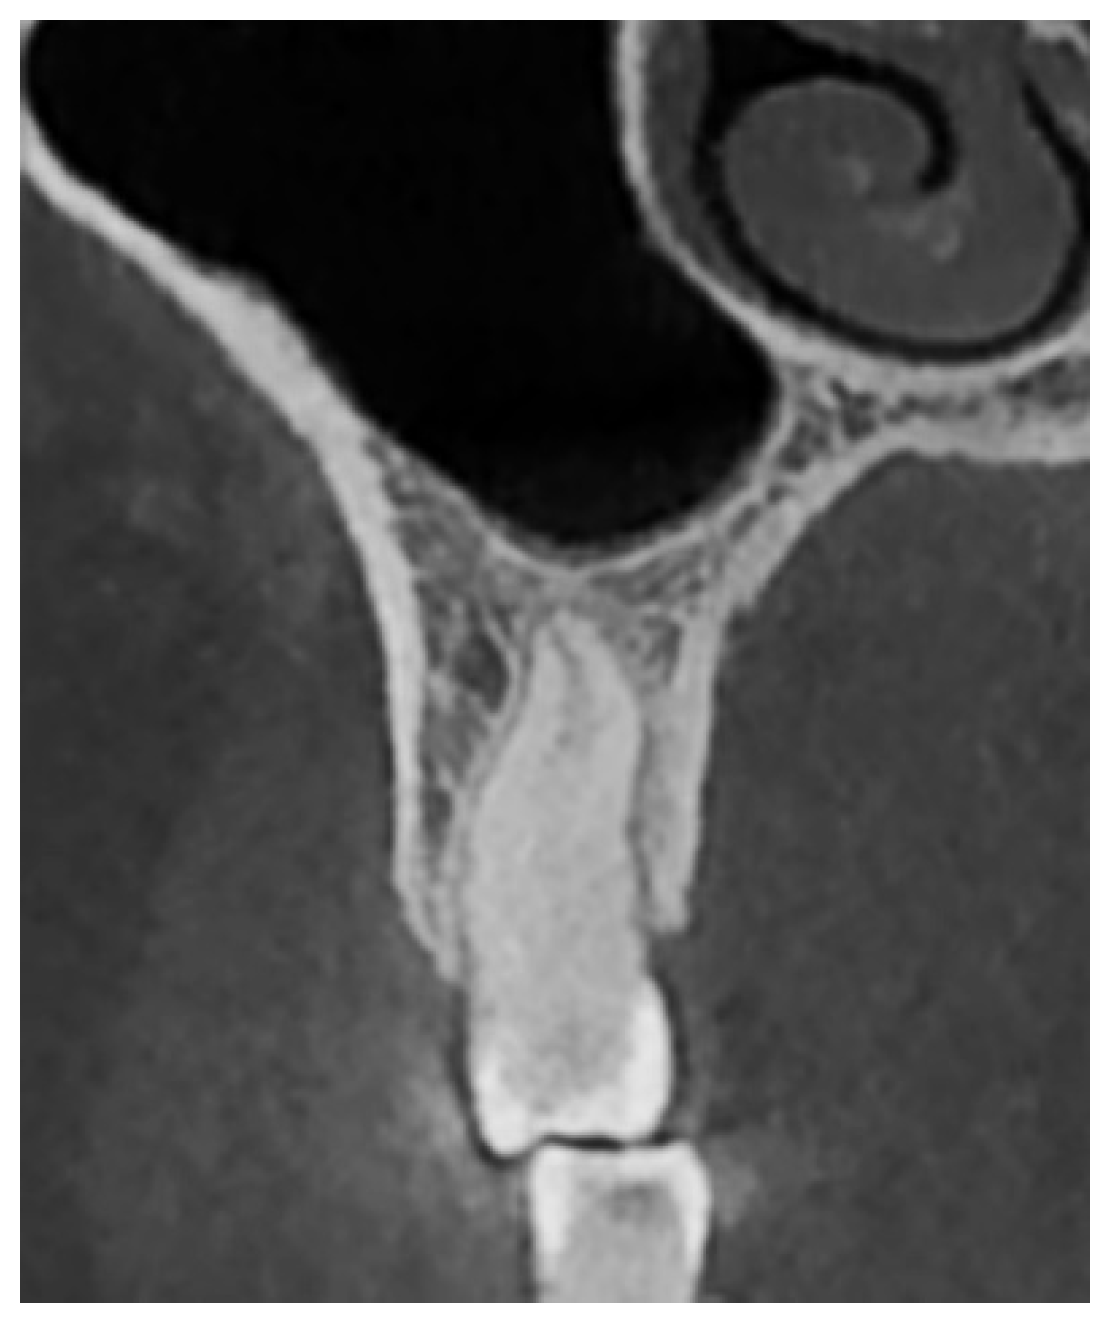

- Type I: Penetrating relationship—the tooth root extends into the maxillary sinus cavity (Figure 2).